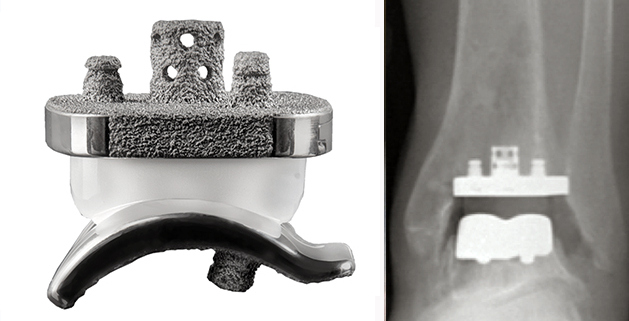

Ankle replacement, also known as total ankle arthroplasty (TAA), is a surgical procedure that aims to replace a damaged ankle joint with an artificial one. This joint replacement has seen increasing popularity as an effective treatment for individuals suffering from end-stage arthritis in the ankle, deformity, pain, and loss of function. It is also an alternative to ankle fusion surgery, which could limit mobility.

There are primarily two categories of ankle replacement designs: mobile-bearing and fixed-bearing implants. Mobile-bearing designs allow for some natural movement and flexibility, while fixed-bearing designs tend to be more stable but with potentially limited mobility.

In cases where non-surgical treatments will not provide relief, ankle replacement surgery could be the best choice. The surgical procedure involves removing the damaged ankle joint and replacing it with an artificial joint.